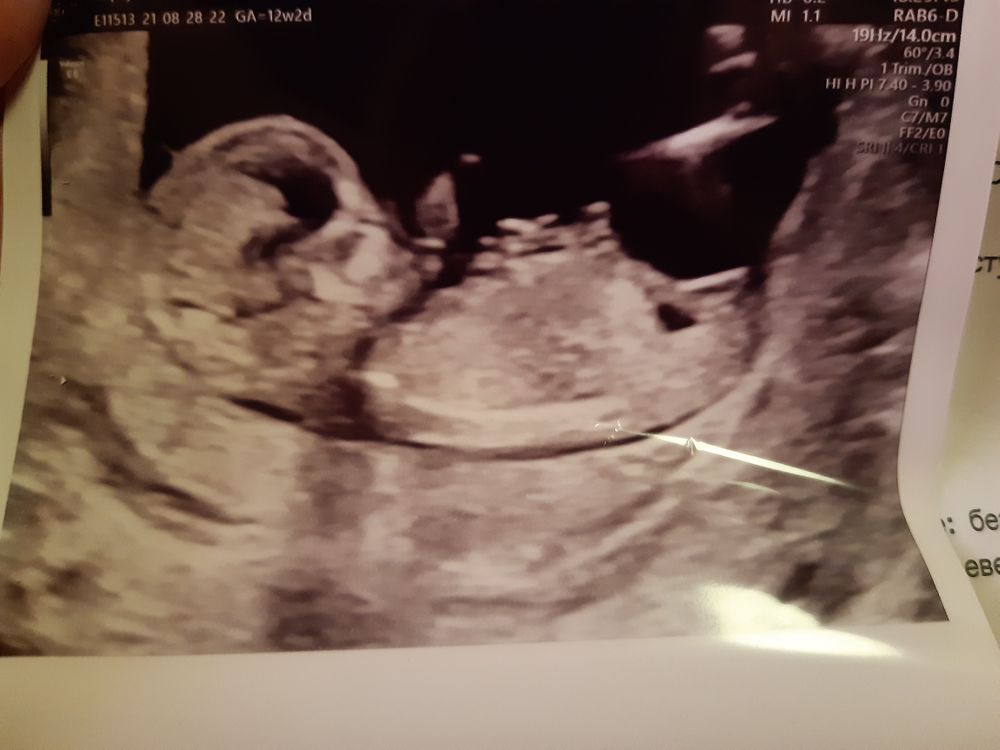

Пол в 12 недель беременности...

Ошибка возможна, но вероятность небольшая, если узи аппарат нормальный и врач опытный. Мне в 12 недель сказали 90% девочка, там по наклону бугорка видно.

На этом сроке возможна ошибка. Лучше повторить узи недель в 15-16